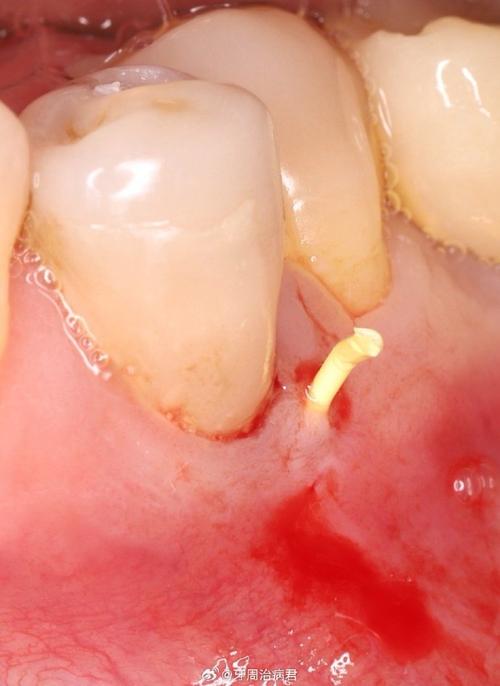

(图片来源网络,侵删) -